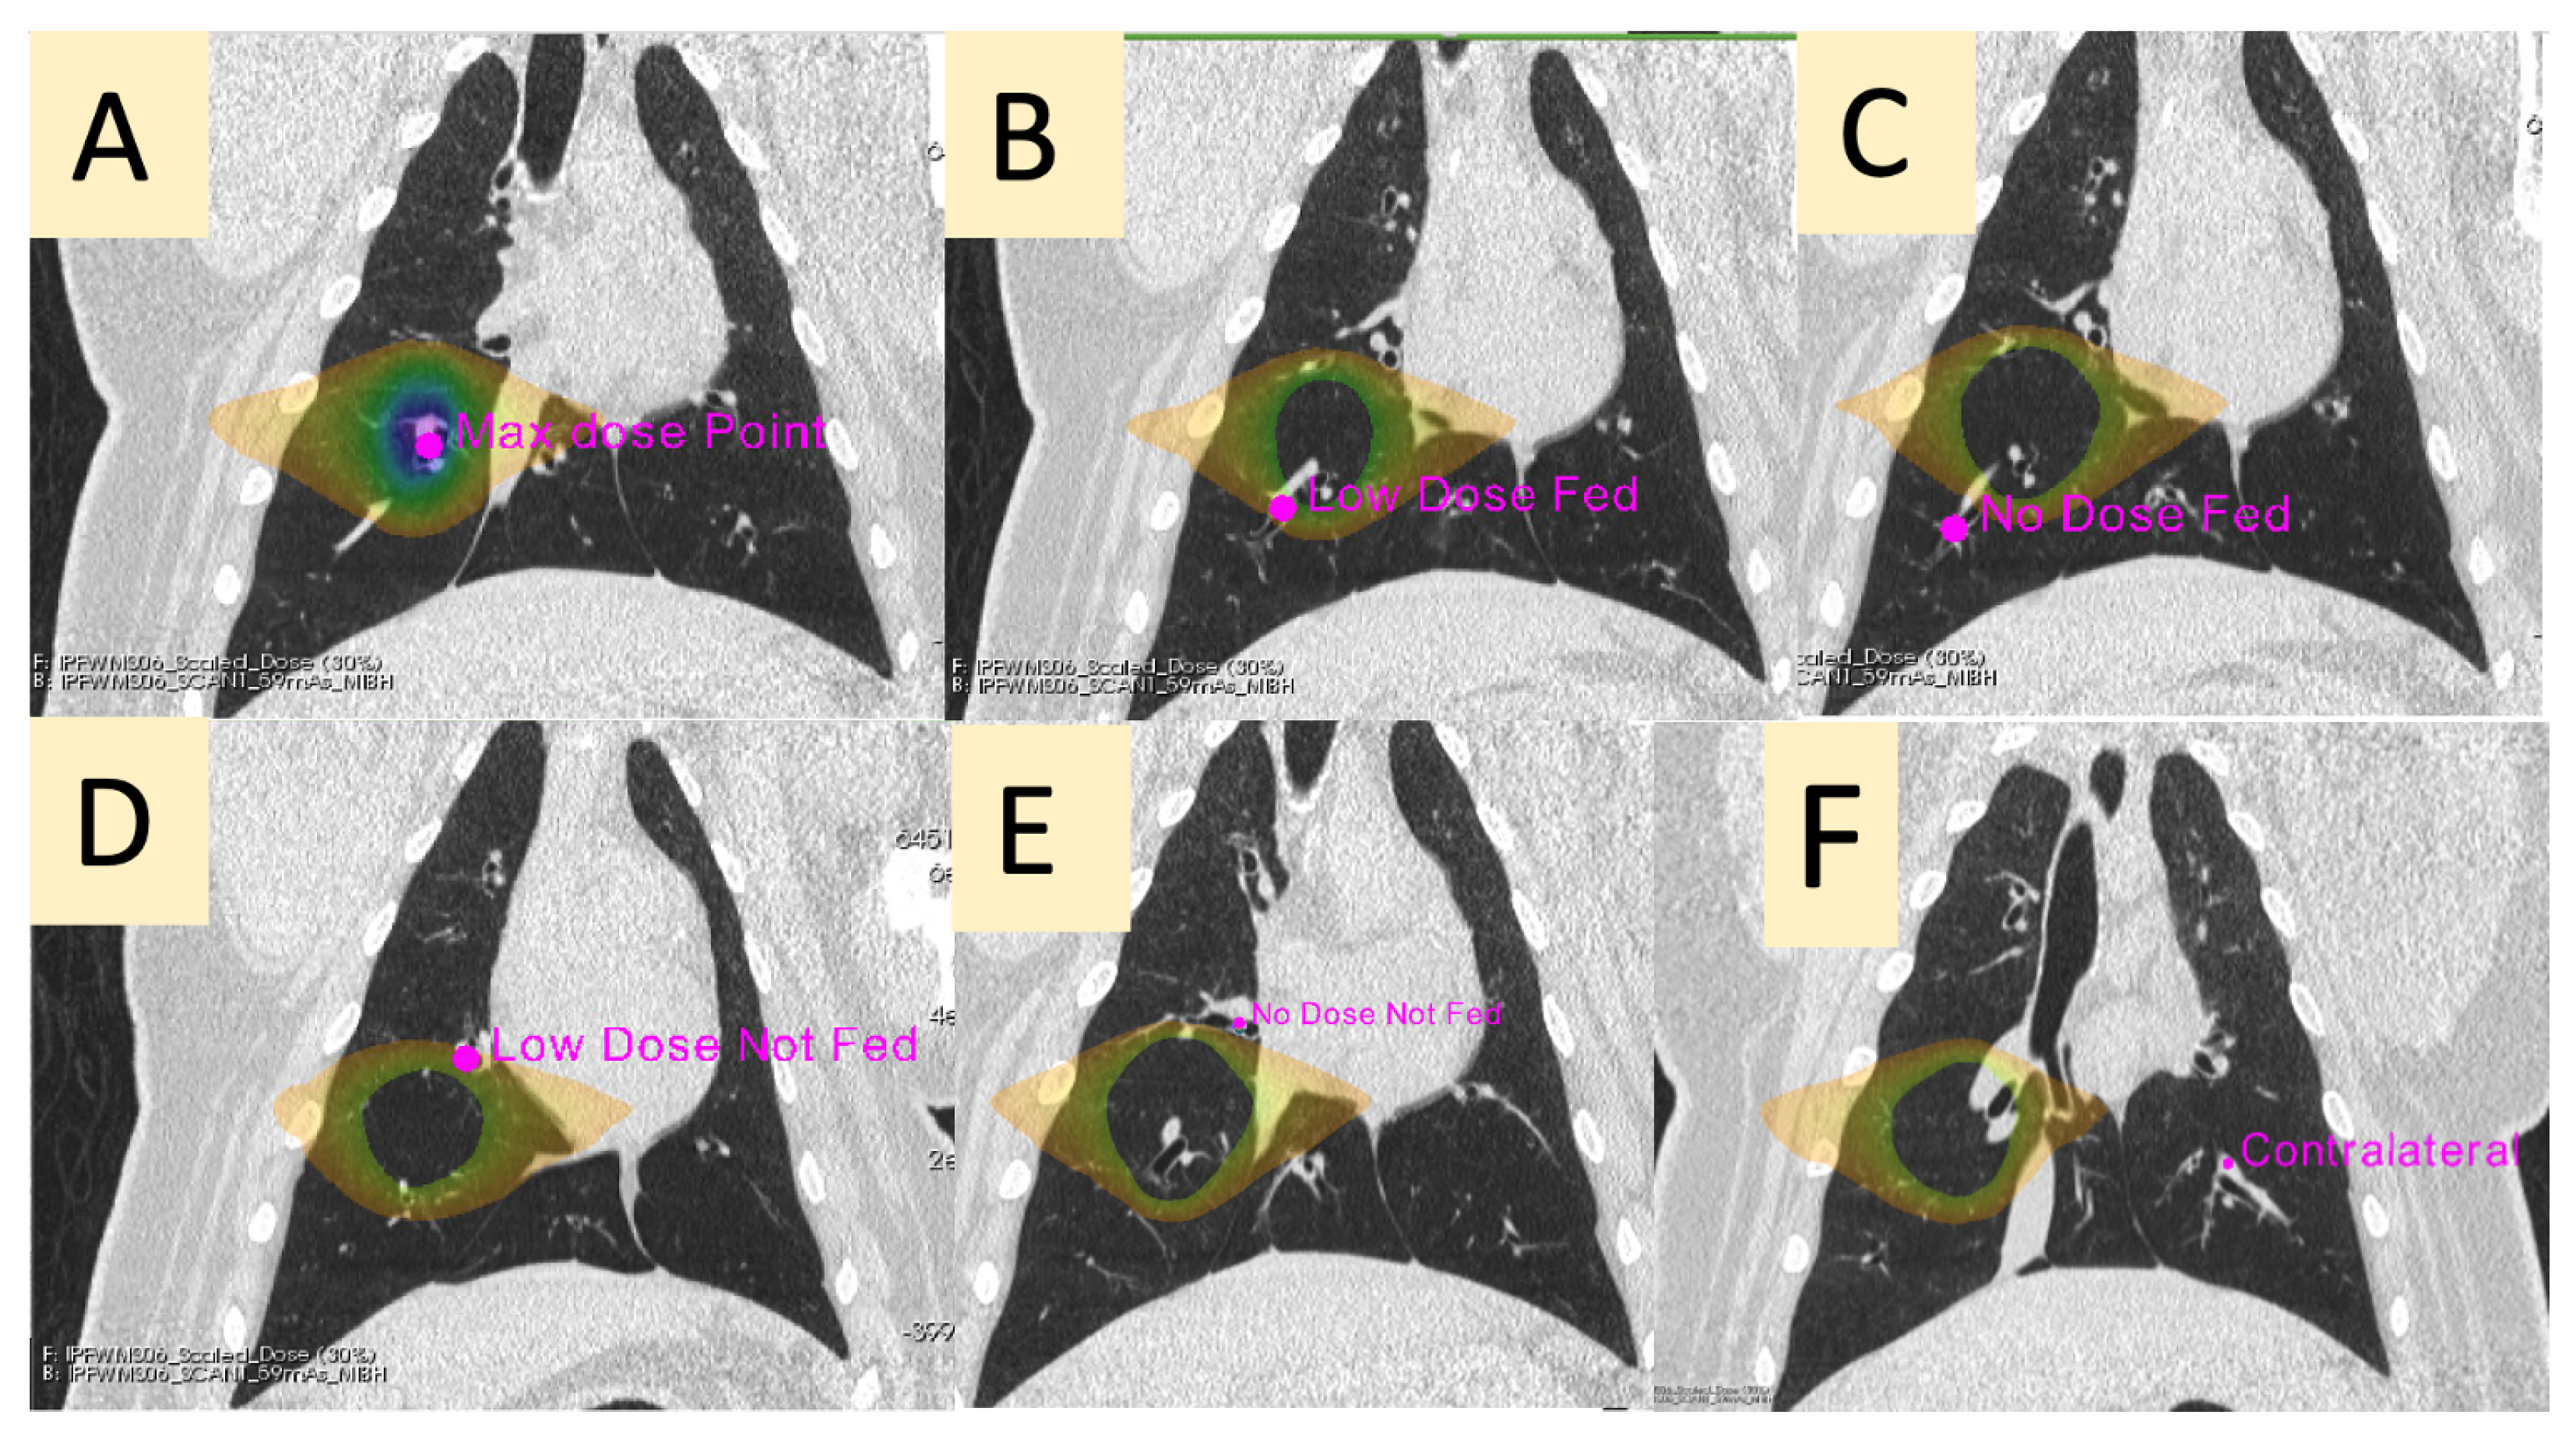

| Contour Name | Description |

|---|---|

| Max Dose (MD) | The vessel contained in the PTV |

| Low-Dose Fed (LDF) | A vessel in the ipsilateral lung receiving between 5 and 20 Gy that branches downstream of the vessel irradiated to the max dose |

| No-Dose Fed (NDF) | A vessel in the ipsilateral lung receiving less than 5 Gy that branches downstream of the vessel irradiated to the max dose |

| Low-Dose Not-Fed (LDNF) | A vessel in the ipsilateral lung receiving between 5 and 20 Gy that does not branch from the vessel irradiated to the max dose |

| No-Dose Not-Fed (NDNF) | A vessel in the ipsilateral lung receiving less than 5 Gy that does not branch from the vessel irradiated to the max dose |

| Contralateral (CON) | A vessel in the contralateral lung (received no dose) at the approximate mirrored location as the point of max dose in the ipsilateral lung |